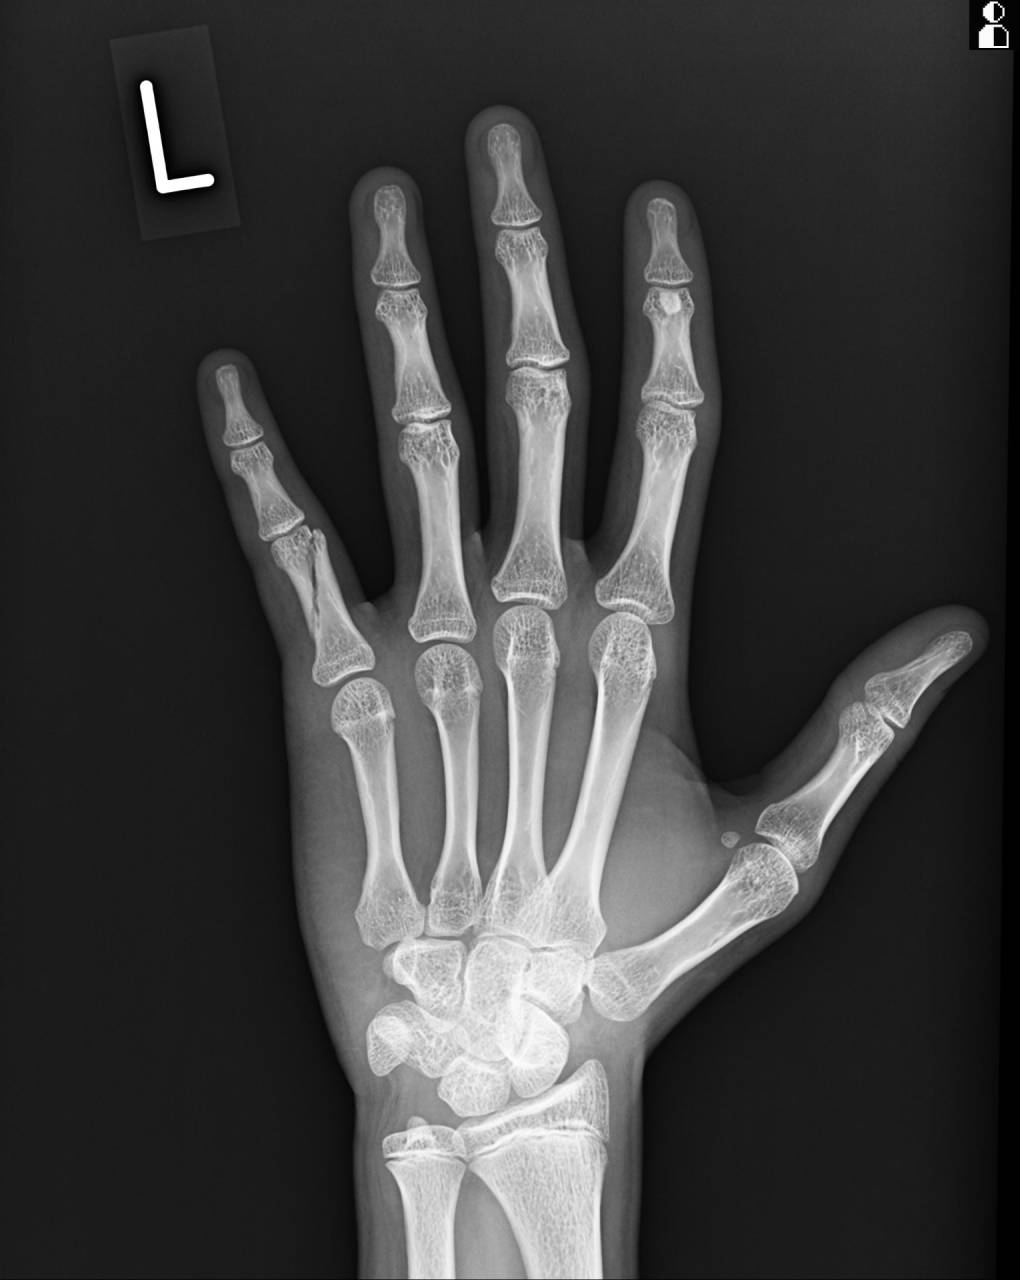

第5指基節骨に骨折線が確認できたので、当整骨院が提携させてもらってる病院にてレントゲン検査の依頼をし撮影してもらいました。

撮影した画像を確認すると、左第5指基節骨斜骨折で病院の先生も手術適応になるものとのことで、大怪我です。

今回の症例は基節骨が斜めに折れていて、背側・外側・短縮転位をしているため整復を行う必要があると同時に固定で転位しないようにしなくてはいけません。

さらに正しく整復・固定を行わないと、骨が修復し、いざ指を曲げようとした時に指同士が重なってしまったり、屈曲に支障が出てくる可能性があるので気をつけてやらねばいけません。

レントゲン画像とエコーを使いながら整復を行います。